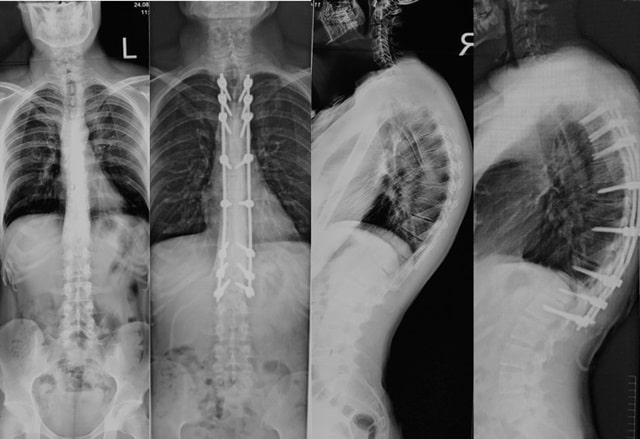

Кіфоз спричиняє біль у спині. У серйозних випадках це може призвести до проблем із диханням або навіть пошкоджень внутрішніх органів через тиск на них. У дитячому віці хребет може деформуватися так, що вирівняти його буде складно або неможливо.

Юнацький кіфоз зазвичай можна виправити за допомогою вправ, фізичної терапії або корекції постави. У деяких випадках потрібне медичне втручання, особливо якщо кіфоз спричиняє біль або обмежує рух. Це може визначити тільки лікар.